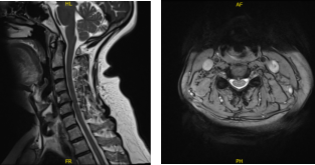

The patient presented results for MRI in cervical spine and showed posteroventral disc herniations at C4-C5 and C6-C7, which indent the ventral thecal sac and ventral cord surface. Annular bulge/vertebral spurring at C5-C6, associated with bilateral uncovertebral spurring, slightly larger on the right.

Findings result in, mass effect on the thecal sac and spinal cord, bilateral foraminal encroachment, and slightly worse on the right. Mild cervical spinal stenosis. Facet joint arthropathy in the upper cervical region, more marked on the left.

MRI Cervical Spine non-contrast